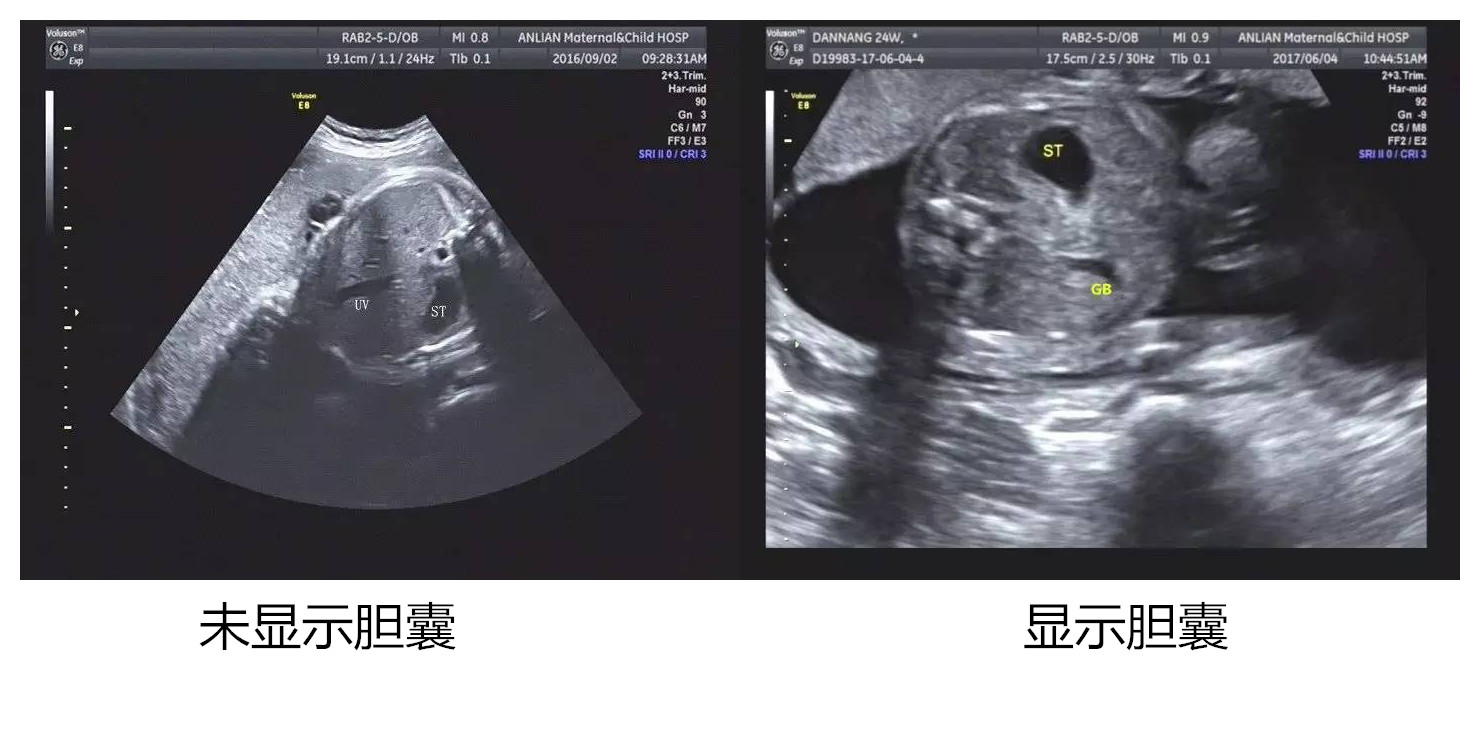

近年,随着产前诊断不断细化、深入,胎儿胆囊作为消化系统的重要组成部分日益受到重视。在孕中晚期超声产前筛查中,偶尔发现胎儿胆囊未见[prenatal non-visualization of fetal gall bladder (PNVGB) ]。当孕妇及家属看到报告单时会恐慌,不安,造成很大心理负担。

造成超声中晚孕期胎儿胆囊未探及的原因分为以下几种:一、孕35周后胎儿胆囊具有明显收缩功能,可能是胆汁排出,胆囊处于收缩状态;二、超声机器的分辨率低、检查医师的经验不足、胎儿的体位不正、肢体遮挡等等,对于过于细小的胆囊结构不能很好的探查和显示;三、发育异常,如囊性纤维化、胆道闭锁、胆囊发育不良等。

首先排除胎儿是否合并染色体异常,如果染色体正常,但羊水穿刺发现消化酶含量低于正常值可以提示胎儿胆道闭锁;如果无其他染色体畸形,消化酶含量也正常可提示仅为单纯性胆囊未显示(发生率1/875)。对于单纯性胆囊未显示医生可以建议定期复查,在孕中晚期、生后、婴儿满月后连续进行超声检查(胎儿必须禁奶、水3-4h),如仍未探查到胆囊可诊断为“胆囊缺如”。根据胎儿临床表现,决定是否继续随访观察。如果合并其他染色体异常,可以建议孕妇终止妊娠。